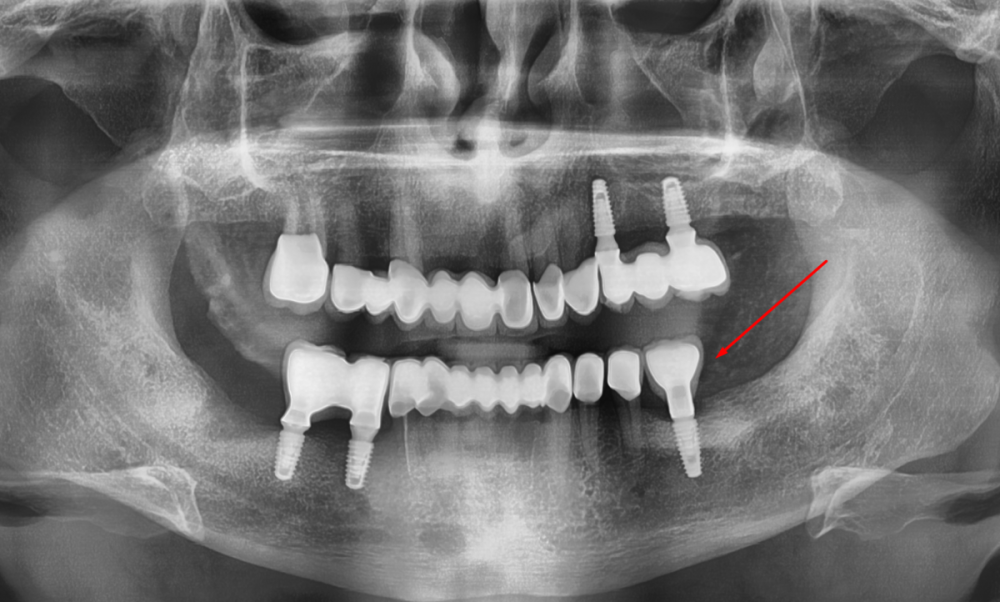

Irouil Опубликовано 8 августа, 2023 Автор Поделиться Опубликовано 8 августа, 2023 Ссылка на комментарий

АнтонТЛТ Опубликовано 8 августа, 2023 Поделиться Опубликовано 8 августа, 2023 Лучше прицельные снимки делать, на таких не рассмотреть ничего. Форум сильно сжимает изображение. Либо кадрировать эти снимки. Почему тибейсы такие короткие используются? Ссылка на комментарий

Irouil Опубликовано 9 августа, 2023 Автор Поделиться Опубликовано 9 августа, 2023 @АнтонТЛТ думаете короткие ти бейсы могут повлиять? Я сейчас не про пассивность. Лаба работает вообще с большим количеством нареканий, самое смешное в этом то, что она наша)) @NazranDantist согласен, есть риски, что какие-то сели внатяг. Ссылка на комментарий

АнтонТЛТ Опубликовано 9 августа, 2023 Поделиться Опубликовано 9 августа, 2023 Разве что короткие тибейсы могут упираться в ткани. Фдм какого диаметра используются на молярах? Ссылка на комментарий